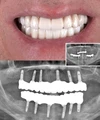

Diş Eksikliği

Periimplantitis